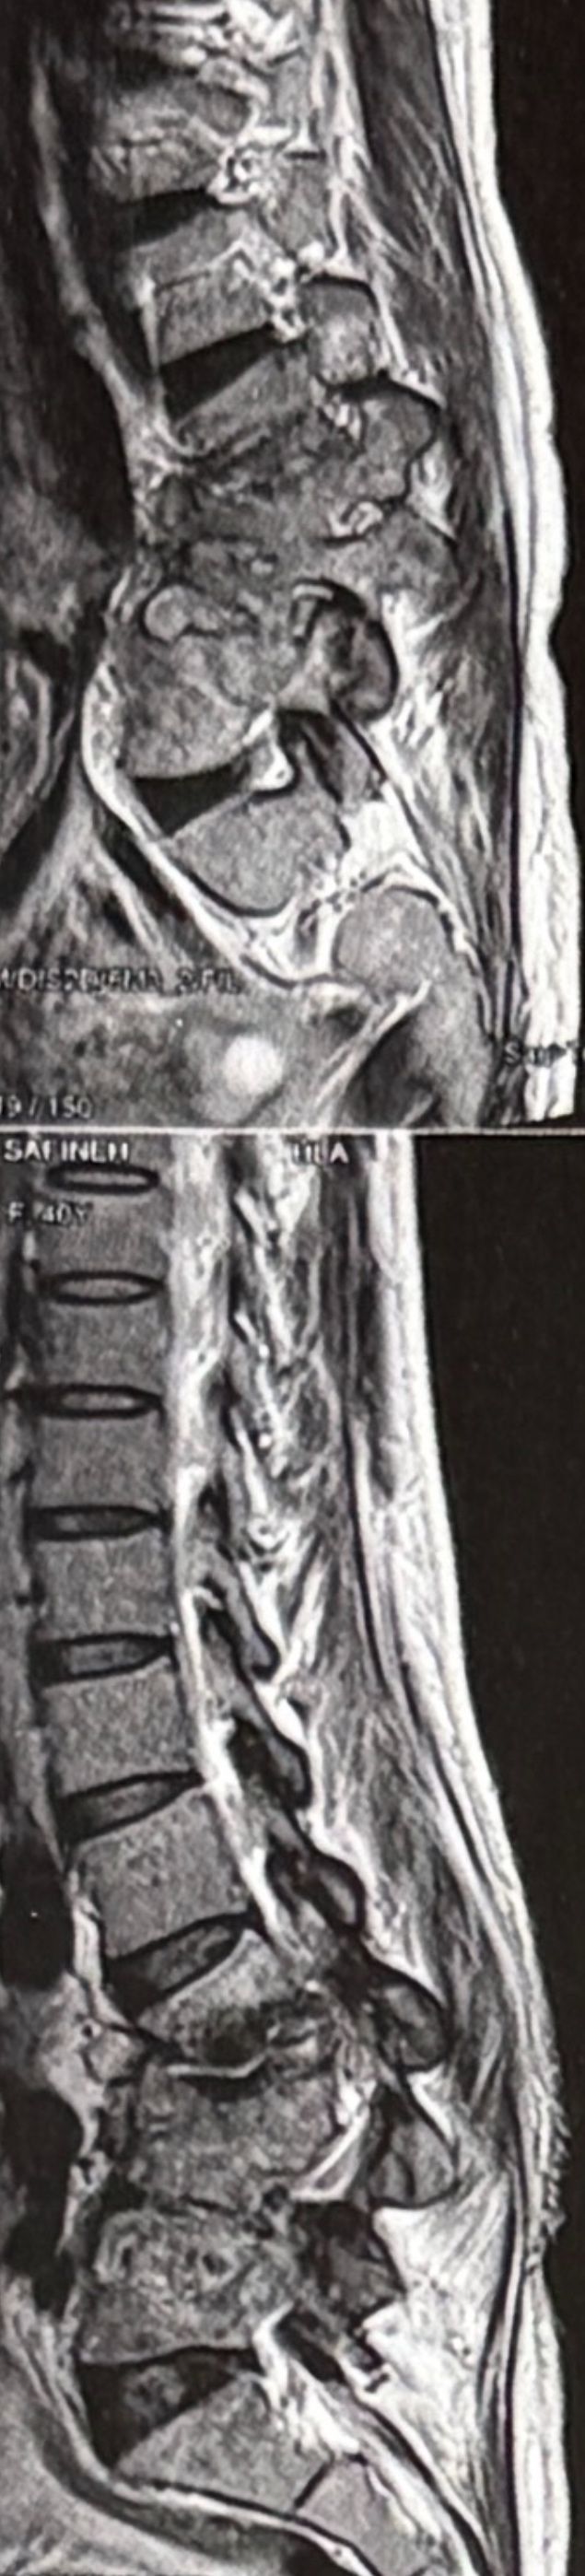

46 years old female patient presented to my clinic yesterday june 1/2025 with LBP and radicular L leg pain for several months which hasn’t responded to physio 2 neurosurgeons have visited her and didn’t suggest any surgery Neurological exam was unremarkable please see her mri/ emg/ncv and her huge tarlov cyst and possible L IVF L4-5 hyperbulge I ordered sacrum mri and ct scan and new emg/ncv and asked her with her sacral Ct scan and MRI first sees another two famous neurosurgeons and see if that large cyst is the reason for her pain if not i can work on her L4-S1 area Do you think her radicular pain can originate from her large cyst in sacrum? Do you consider surgery and removing her sacral cyst?

32 years female patient presented to my office one year ago with moderate cervical pain and R. Arm pain ,mild LBP with no radicular pain. Her mri in C/s had few bulges and few segmentsl dysfunctions

Her lumbar mri showed Contained R. Para. L5-S1 extrusion

She got treatment just for her neck and exercises for her low back. Few months later had lumbar disc surgery

Few days ago on may on june 08/2025, presented with severe LBP and no radicular pain

I have post her lumbar MRI before and after surgery. I consulted with a neurosurgeon at our clinic and he said doesn’t need another surgery because doesn’t have radicular pain or neurological deficits

For her pain i have started to do mild decompression by Cox and DTS and acupuncture, no adjustment whatsoever.

Please mention what differences you see before and after surgery